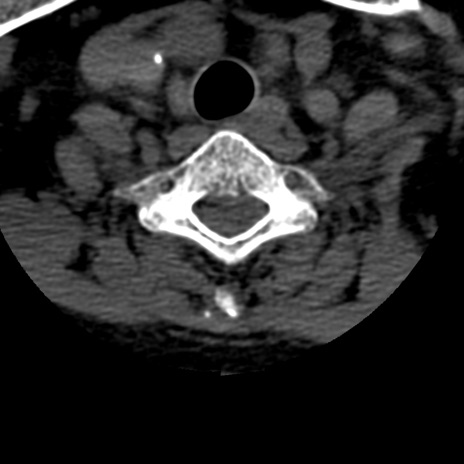

症例50 頚椎CT(横断像)

頚椎CT